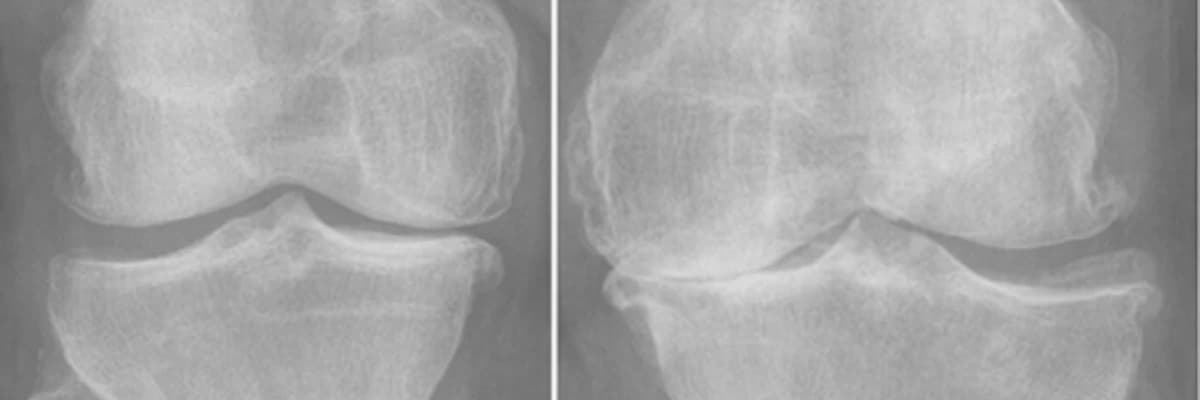

Röntgen veya MR’da ciddi eklem hasarının görülmesi

Muayene ve tetkikler: Röntgen, MR, kan tahlilleri yapılır.